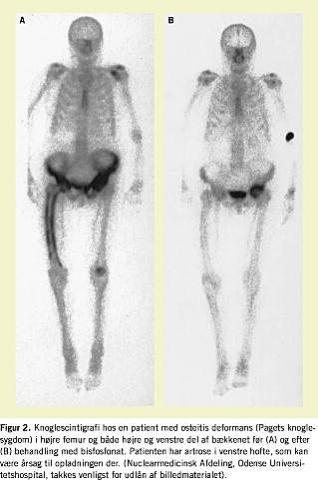

Kun calcitonin og etidronat er registreret til behandling af OD i Danmark, men calcitonin er ineffektivt, og etidronat i effektive doser medfører risiko for mineralisationsdefekt. Intravenøs pamidronat 60 mg hver 3. md., peroral alendronat 40 mg pr. dag i 6 mdr. eller peroral risedronat 30 mg pr. dag i 2 mdr. bør derfor foretrækkes. Zolendronat synes lovende, men dosering og doseringsinterval er endnu ikke afklaret. Calcitonin har i dag kun plads i behandlingen ved mistanke om Pagetic steal- syndrom. Behandling med bisfosfonater fortsættes indtil knogleomsætningen vurderet ved serum-basisk fosfatase (AP) er normaliseret (typisk efter 6-24 mdr.s behandling). Derefter følges serum AP hver 3.-6. md. og behandlingen gentages, hvis serum-AP stiger mere end ca. 25% over øvre normalværdi. Man kan vælge at fortsætte behandlingen indtil knoglescintigrafi viser normaliserede forhold (Figur 2 ), men fordelen ved dette er ikke dokumenteret.

Taksigelse: Nuclearmedicinsk Afdeling, Odense Universitetshospital, takkes for udlån af billedmaterialet.